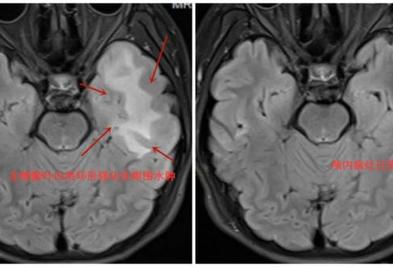

关注|14岁的少年突发癫痫,竟然和养猫有关?大夫提醒! 青少年突发癫痫,忧心忡忡。 脑科专家顺藤摸瓜抓出原因 原来养猫的清洁不到位 感染性寄生虫对大脑有害 产生异常放电 现在,经过一个月的驱虫治疗 患者的颅内疾病已经完全吸收 病人检查图像。通讯员周珊 摄 2024-11-22